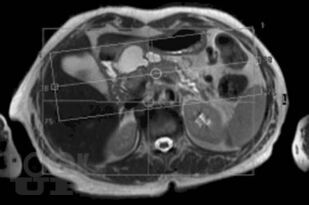

В монографии представлены современные сведения о магнитно-резонансной холангиопанкреатографии (МРХПГ). Детально отражены технические основы метода, методика и планирование исследования. Рассматриваются причины ошибок при интерпретации данных МРХПГ и способы их предотвращения и преодоления. Приведены базовые протоколы различных видов МРХПГ. Описана нормальная анатомия желчевыводящих протоков, желчного пузыря и протоков поджелудочной железы, изменения желчевыводящих протоков, желчного пузыря и протоков поджелудочной железы при патологических процессах. Отражены вопросы диагностики холангиолитиаза и оценки послеоперационной анатомии желчевыводящих протоков. Рассмотрены особенности МРХПГ при патологических изменениях комплекса большого дуоденального сосочка и двенадцатиперстной кишки. Приведены данные о МРХПГ с использованием гепатоспецифического контрастного вещества.